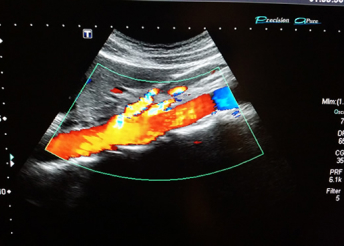

Ultrazvuk krvnih sudova

Ovaj pregled je neinvazivna bezbolna dijagnostička metoda kojom se meri protok krvnih sudova vrata, ruku ili nogu, registruju suženja na arterijskum krvnim sudovima, proširenja istih (aneurizme) ili postojanje tromboze ili proširenja u venskim krvnim sudovima.